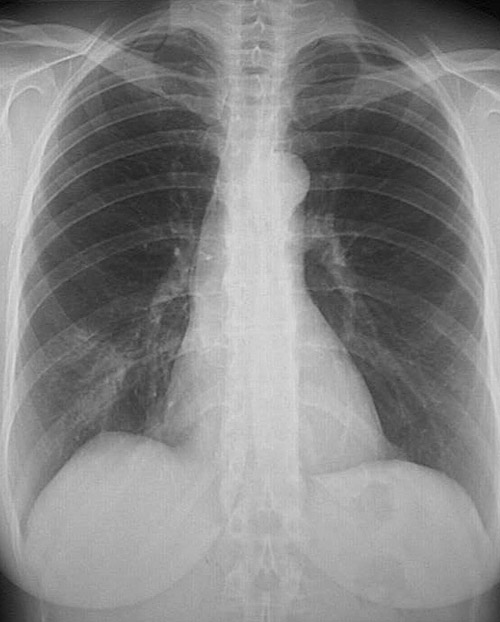

She returns to her physician 4 years later with a 2 day history of fever with worsening cough productive of a small amount of yellowish sputum. On examination her temperature is 39 C, pulse 93/min, respiratory rate 22/min, and blood pressure 110/65 mm Hg. There are crackles auscultated at the right lung base.

A chest x-ray is ordered.

Figure 2: Chest x-ray.